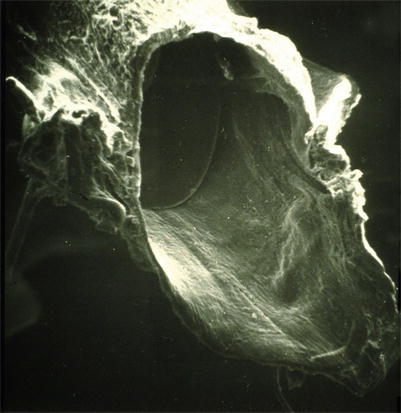

Lympho-lymphatic anastomoses have been investigated also by electron microscopy. Electron microscopy investigations revealed a smooth inner surface at the site of the anastomosis. In Fig. 2.11, the area of a lympho-lymphatic anastomosis is opened by an oblique cut of the vessel. The nonabsorbable suture material marks the site of the anastomosis. The vessel is stabilized by a small round insert for the electron microscopy preparation. The anastomosis is patent, the inner surface is smooth, and the endothelial layer is continued from one vessel to the other (Fig. 2.11).

Fig 2.11

Scanning electron microscopy (oblique cut of the anastomosing site) 11 weeks after lympho-lymphatic anastomoses (nonabsorbable suture material), patent anastomosis, smooth inner surface continuous endothelial layer